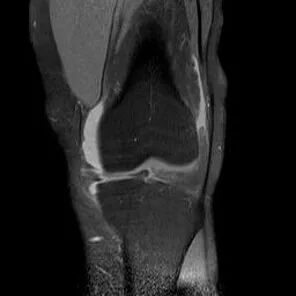

最常见类型:斜行撕裂表现为:在矢状面上见III级高信号到达半月板关节面的上缘或下缘

半月板斜行撕裂